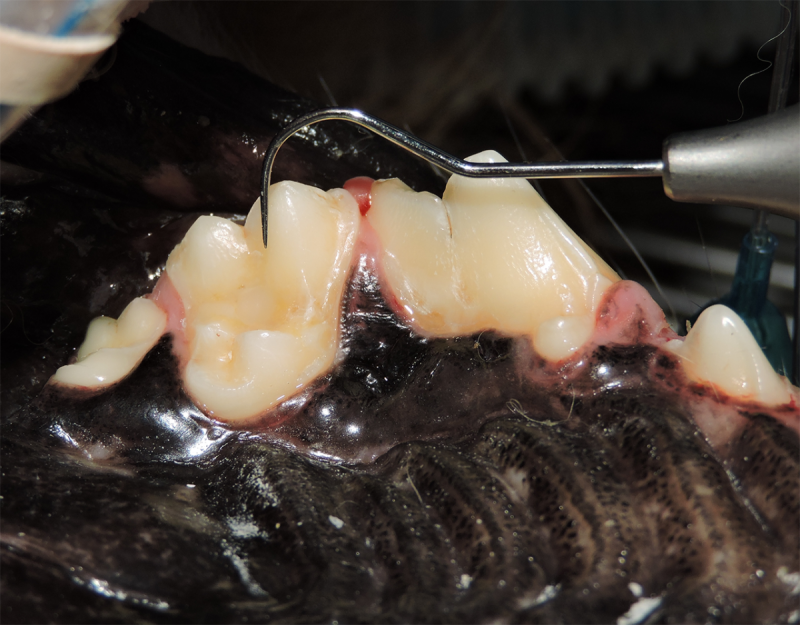

Tooth Resorption

Tooth resorption is a disease process where the body begins to break down the adult tooth. It is widely known to occur in cats but can also occur in dogs. In cats these lesions are thought to be inflammatory, while in dogs they can be more of a replacement resorption process. These lesions can be very painful and should be treated, generally with extraction depending on the type of resorption that is occurring. The disease can be progressive and affect many teeth over several years. It is important to have regular checkups and yearly dental cleanings to monitor for these lesions.